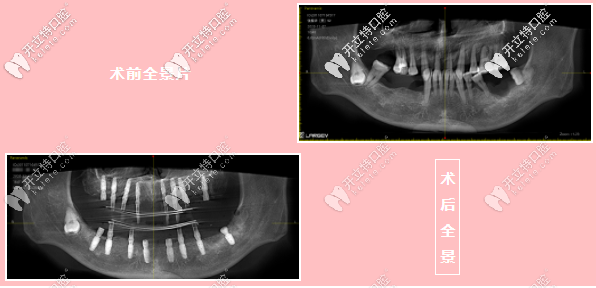

陳先生術(shù)前術(shù)后全景對比圖

【術(shù)前術(shù)后對比圖】